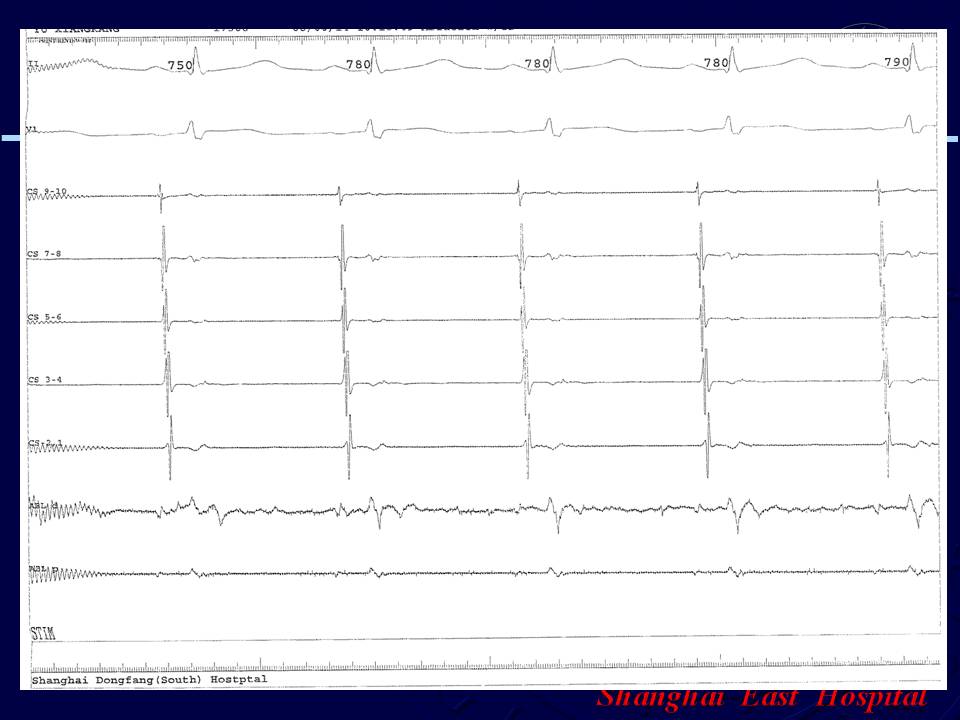

阵发性房颤、无冠窦房早射频消融1例

谭红伟 张旭敏 邹誉 周建 刘学波